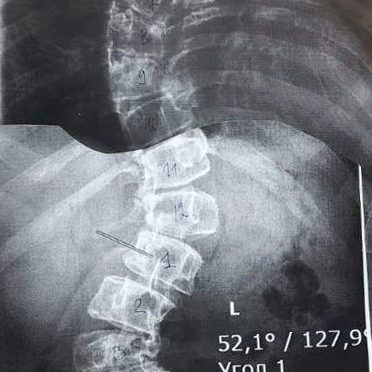

17-летняя пациентка поступила в больницу с S-образным сколиозом 3-4 степени. Это тяжелая форма искривления позвоночника — для неё характерна выраженная деформация, которая вызывает ярко выраженный болевой синдром и существенно ограничивает подвижность. Кроме того, такая патология несет серьезную угрозу развития осложнений со стороны внутренних органов и может спровоцировать возникновение сопутствующих заболеваний. Консервативные методы лечения в данном случае были бы малоэффективны и специалисты приняли решение провести сложную, трудоемкую операцию по исправлению деформации и фиксации нормального положения позвоночника.

«Сколиоз – это ортопедическое заболевание, которое характеризуется сложной деформацией одновременно в нескольких плоскостях позвоночного столба и грудной клетки. Сопровождается нарушением функции органов и систем организма, является причиной тяжелых физических и психологических трудностей у детей. Обычно бывает достаточно комплексного консервативного лечения: это лечебная гимнастика, массаж, корсеты и другие методы. Редко, при работе с особенно тяжелыми случаями, требуется хирургическое вмешательство. В нашей больнице такую операцию проводили впервые, она заняла около десяти часов, потребовалась слаженная работа высококвалифицированных специалистов разного профиля – анестезиологов, нейрофизиологов, трансфузиологов, нейрохирургов, травматологов-ортопедов. В ходе хирургического вмешательства применили современный метод коррекции сколиотической деформации. Вдоль позвоночника на разных уровнях установили транспедикулярные винты. Затем на них слева и справа наложили специальные стержни, предварительно изогнутые с учетом коррекции деформации позвоночника и физиологических изгибов, они были закреплены гайками. Это конструкция позволила зафиксировать нормальное положение позвоночника и исправить искривление», — рассказал Исмаил Османов.